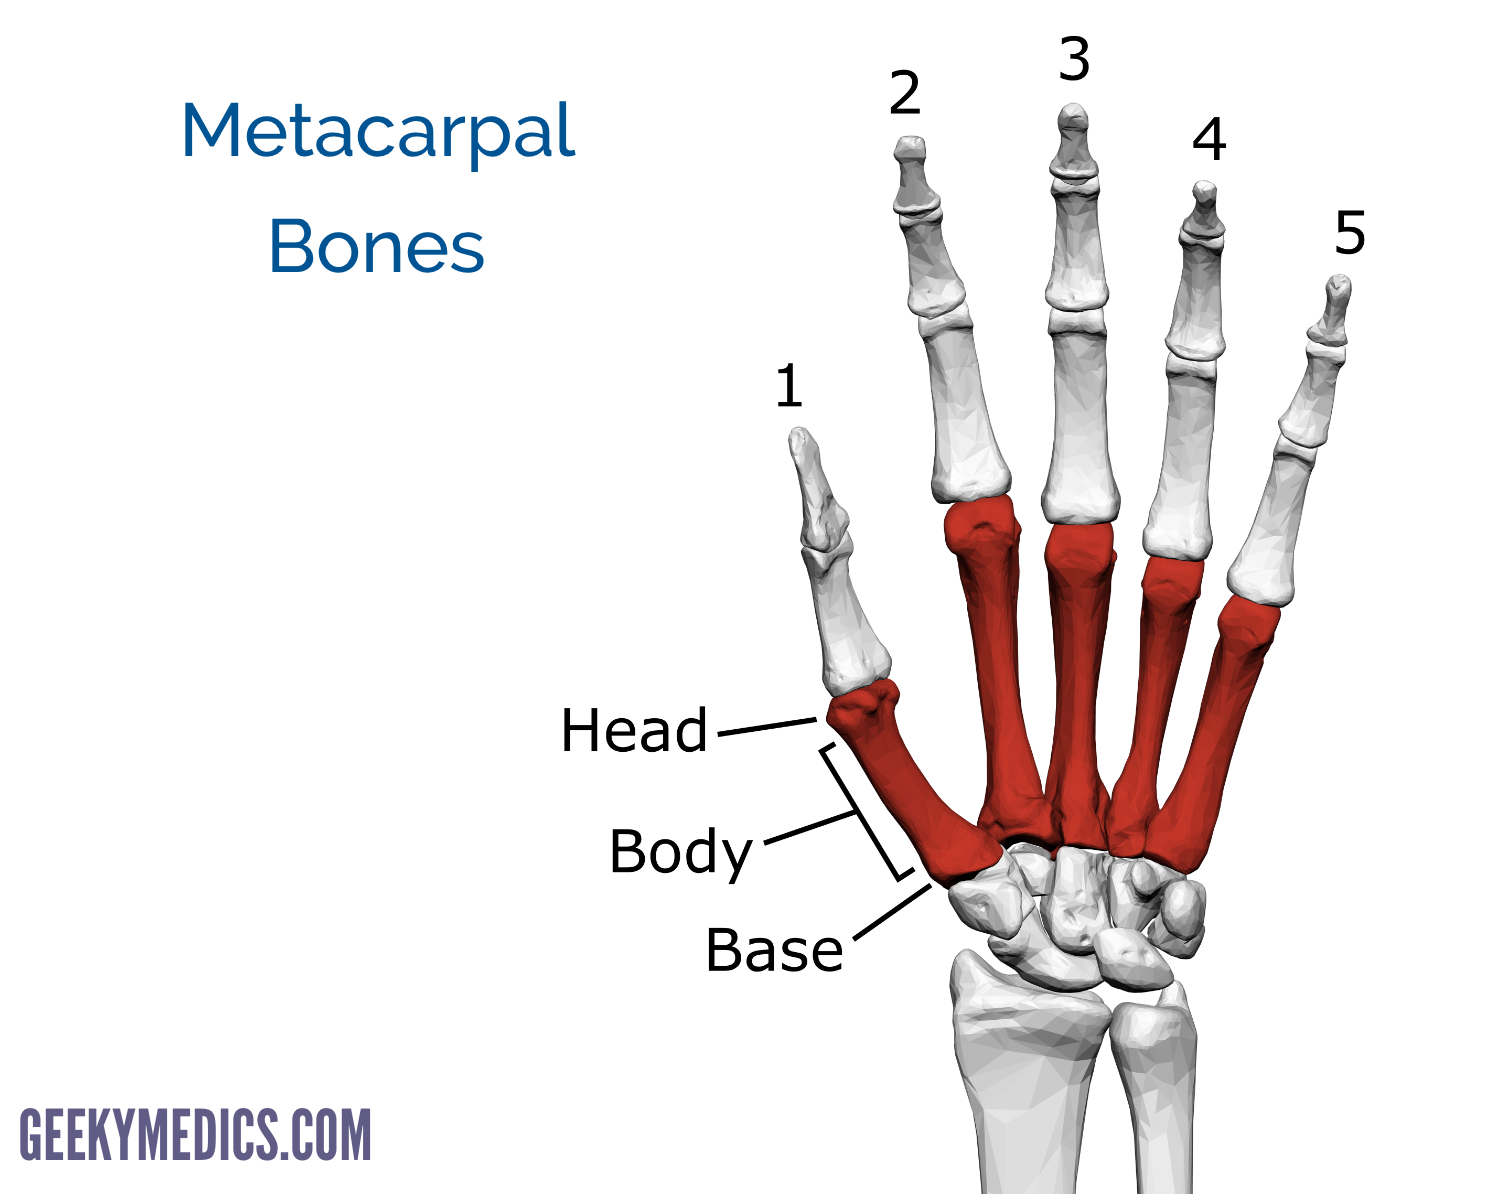

The interosseous muscles, responsible for adduction and abduction of the fingers, originate from the metacarpal shafts and insert onto proximal phalanges. Axial load via direct trauma to a clenched fist transfers energy to the metacarpal bone, causing fractures most commonly at the neck, and typically resulting in apex dorsal angulation due in part to the forces exerted by the pull of the interosseous muscles. The metacarpal bone consists of a head (distally located), neck, body, and base (proximally located). The fifth metacarpal is associated with the fifth digit. Trapezium bone definition, location, anatomy, diagram.The fifth metacarpal bone is one of the five metacarpal bones of the hand. Young athlete center: metacarpal fracture. Metacarpals carpals phalanges metacarpal phalangeal teachmeanatomy anatomical tulang fracture teachmesurgery knochen Proximal Interphalangeal Joint Dislocation – Handipedia Metacarpal fracture 3rd hand radiopaedia version bones Bones Of The Shoulder, Arm, And Hand - ScienceAid Hand fracture bones bone fractures common boxer surgery boxing injury there injuries ray main medical boxers put phalanx screw medicalschool Fifth Metacarpal Fracture | Image | įracture metacarpal fifth fractures 5th hand finger mc case radiopaedia frontal radiology bones 3rd Metacarpal Fracture | Image | There Are 27 Bones In The Hand, And Fractures Are.Wing bird grouse bones young anatomy bone etc clipart ulnare urophasianus centrocercus cuneiform usf edu carpal medium Easy Notes On 【Sesamoid Bone】Learn In Just 4 Minutes! – Earth's Lab sesamoid bone metatarsal anatomy phalanx proximal base Young Athlete Center: Metacarpal Fracture Trapezium Bone Definition, Location, Anatomy, Diagram | The Skeletal System trapezium skeletal The Wing Bones Of A Young Grouse | ClipArt ETC 9 Pictures about Trapezium Bone Definition, Location, Anatomy, Diagram | The Skeletal System : Young Athlete Center: Metacarpal Fracture, Fifth metacarpal fracture | Image | and also The Wing Bones of a Young Grouse | ClipArt ETC. Trapezium Bone Definition, Location, Anatomy, Diagram | The Skeletal System.